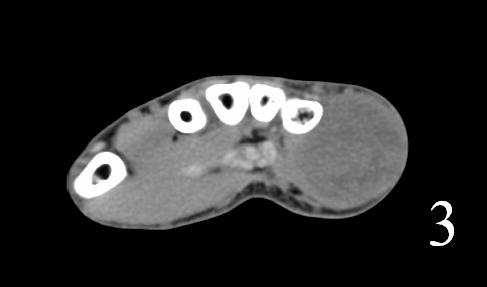

CT

- Shows a heterogeneous mass sometimes involving adjacent bone

- After contrast, the mass enhances (Fig. 2, Fig. 3)

- Hard to identify necrosis, hemorrhagic or calcification.

Fig. 2-3: Coronal and axial (Fig. 3) CT of a rhabdomyosarcoma of the hand shows a well circumscribed mass isointense to muscle